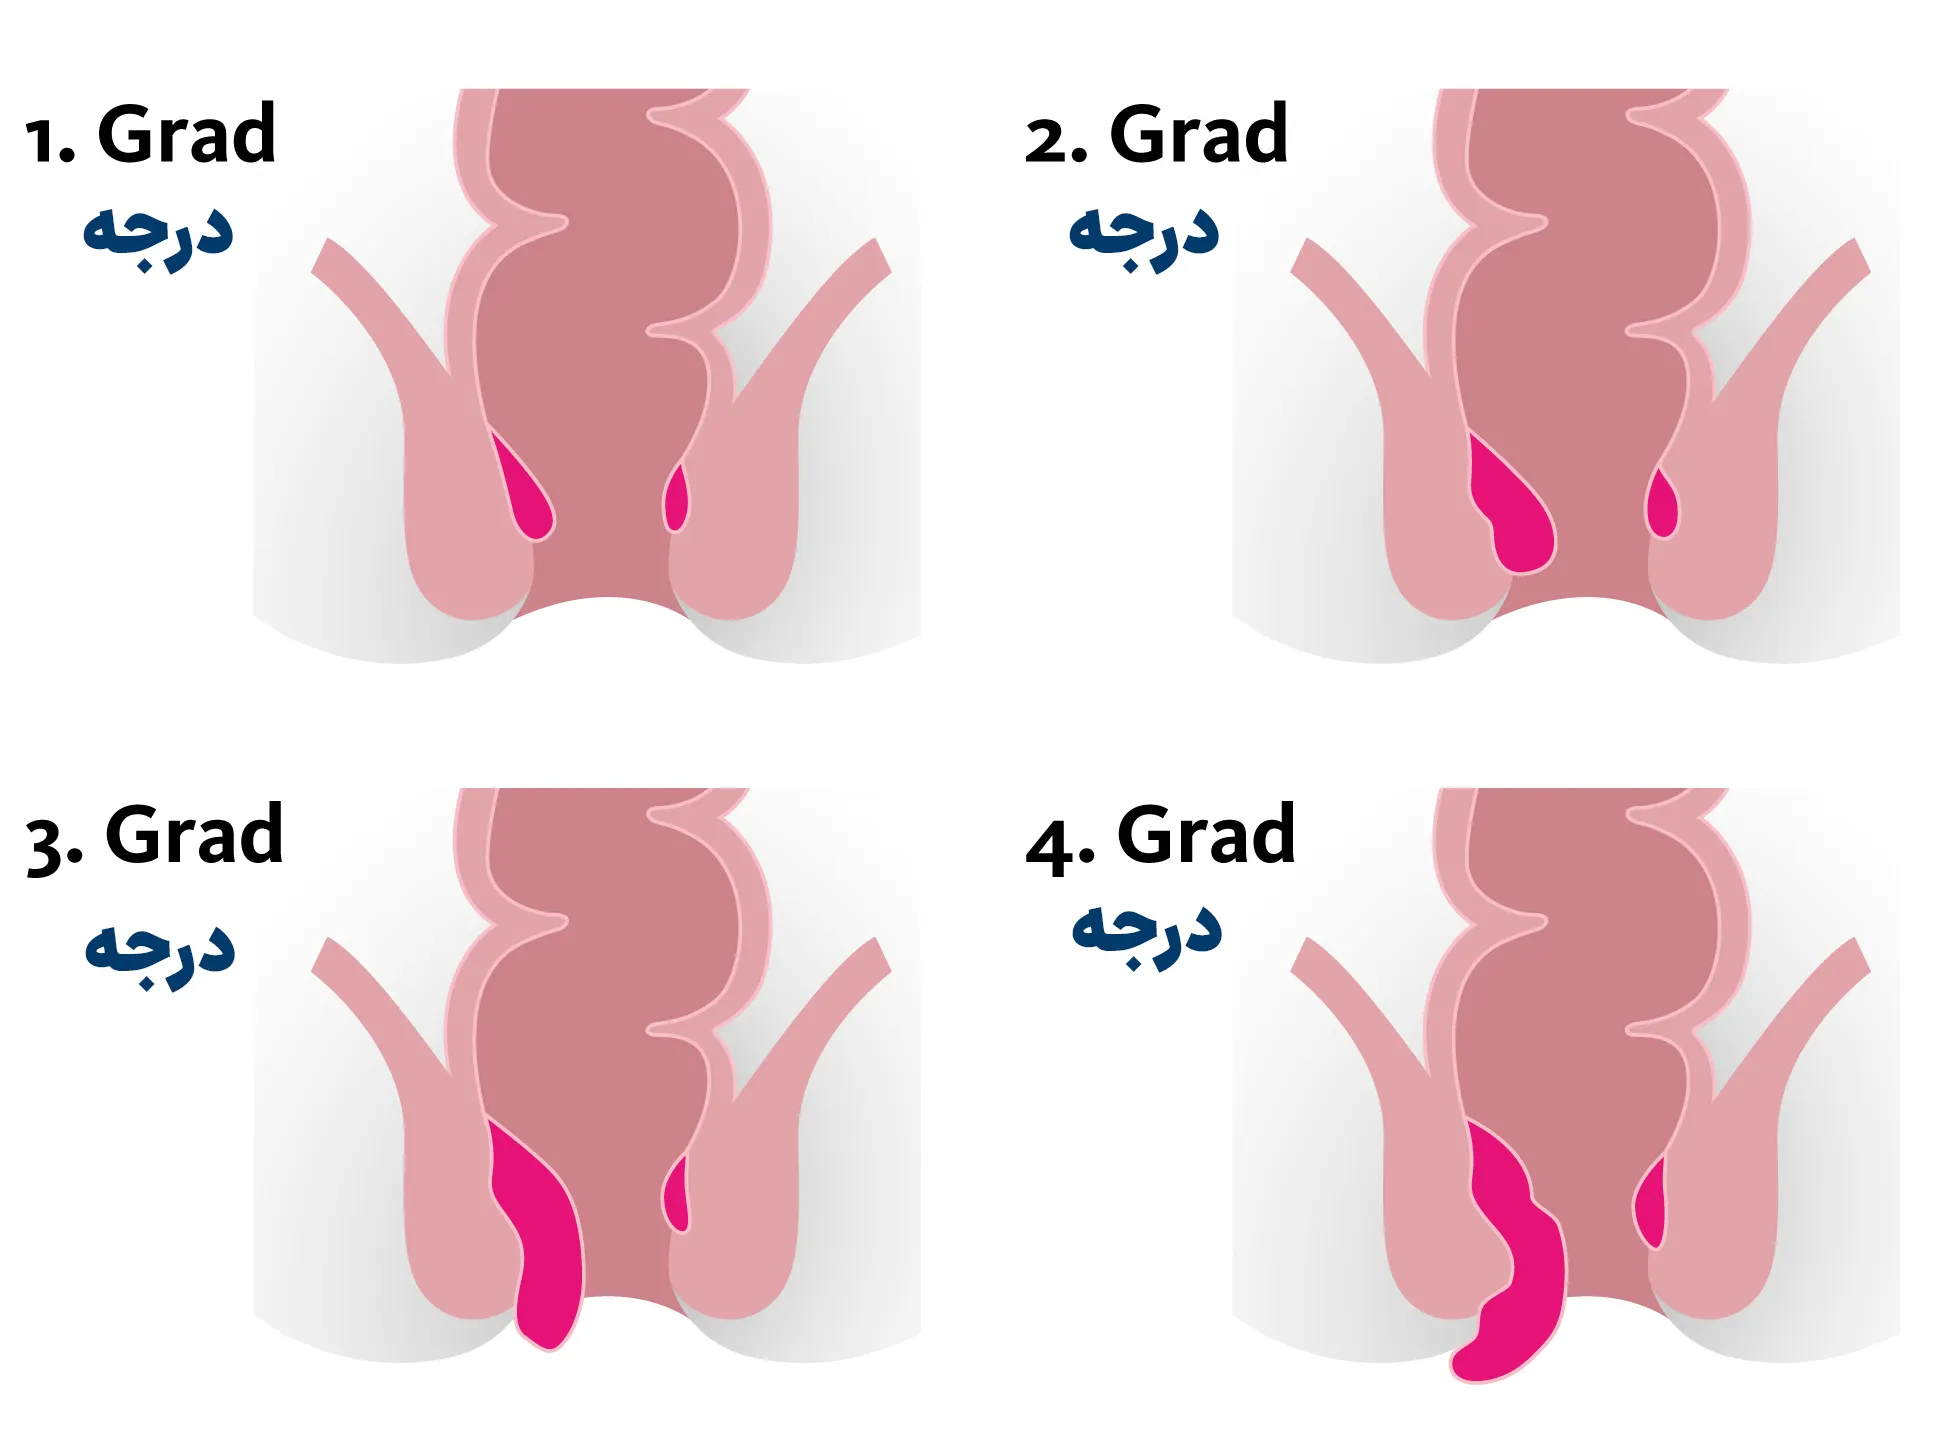

هموروئید انواع مختلفی دارد و هر یک از آنها نیز بر اساس علائم به گریدهای مختلفی دسته بندی می شوند. انواع هموروئید عبارتند از:

هموروئید داخلی رگ های ملتهب و متورم داخل رکتوم هستند که معمولا بدون درد بوده و مهمترین علائم آنها خونریزی هنگام اجابت مزاج است. هموروئید خارجی به وریدهای متورم اطراف دهانه مقعد گفته می شود که با درد و ناراحتی و سوزش در اطراف مقعد مشخص می شود.